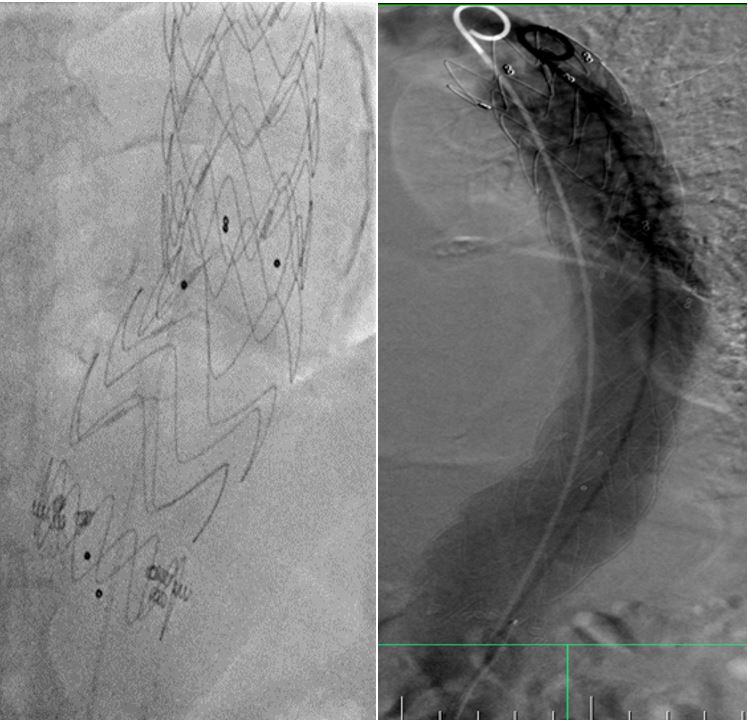

Stredoslovenský ústav srdcových a cievnych chorôb patrí k vedúcim centrám v endovaskulárnej liečbe výdutí a disekcií aorty na Slovensku. Prístroj vďaka integrovanému intravaskulárnemu ultrazvuku a najmodernejšiemu softwarovému vybaveniu, vrátane 2D/3D navigácie a fúzie s CT obrazom, ďalej posúva možnosti terapie a umožní bezpečnejšiu liečbu aj tých najkomplikovanejších prípadov.

Pacient s objemnou výduťou hrudnej aorty s krátkou implantačnou zónou ošetrený za pomoci 3D navigácie hrudným stentgraftom a fixovaný pomocou endoskrutiek za účelom zabránenia neskorej migrácie (posunu) graftu.